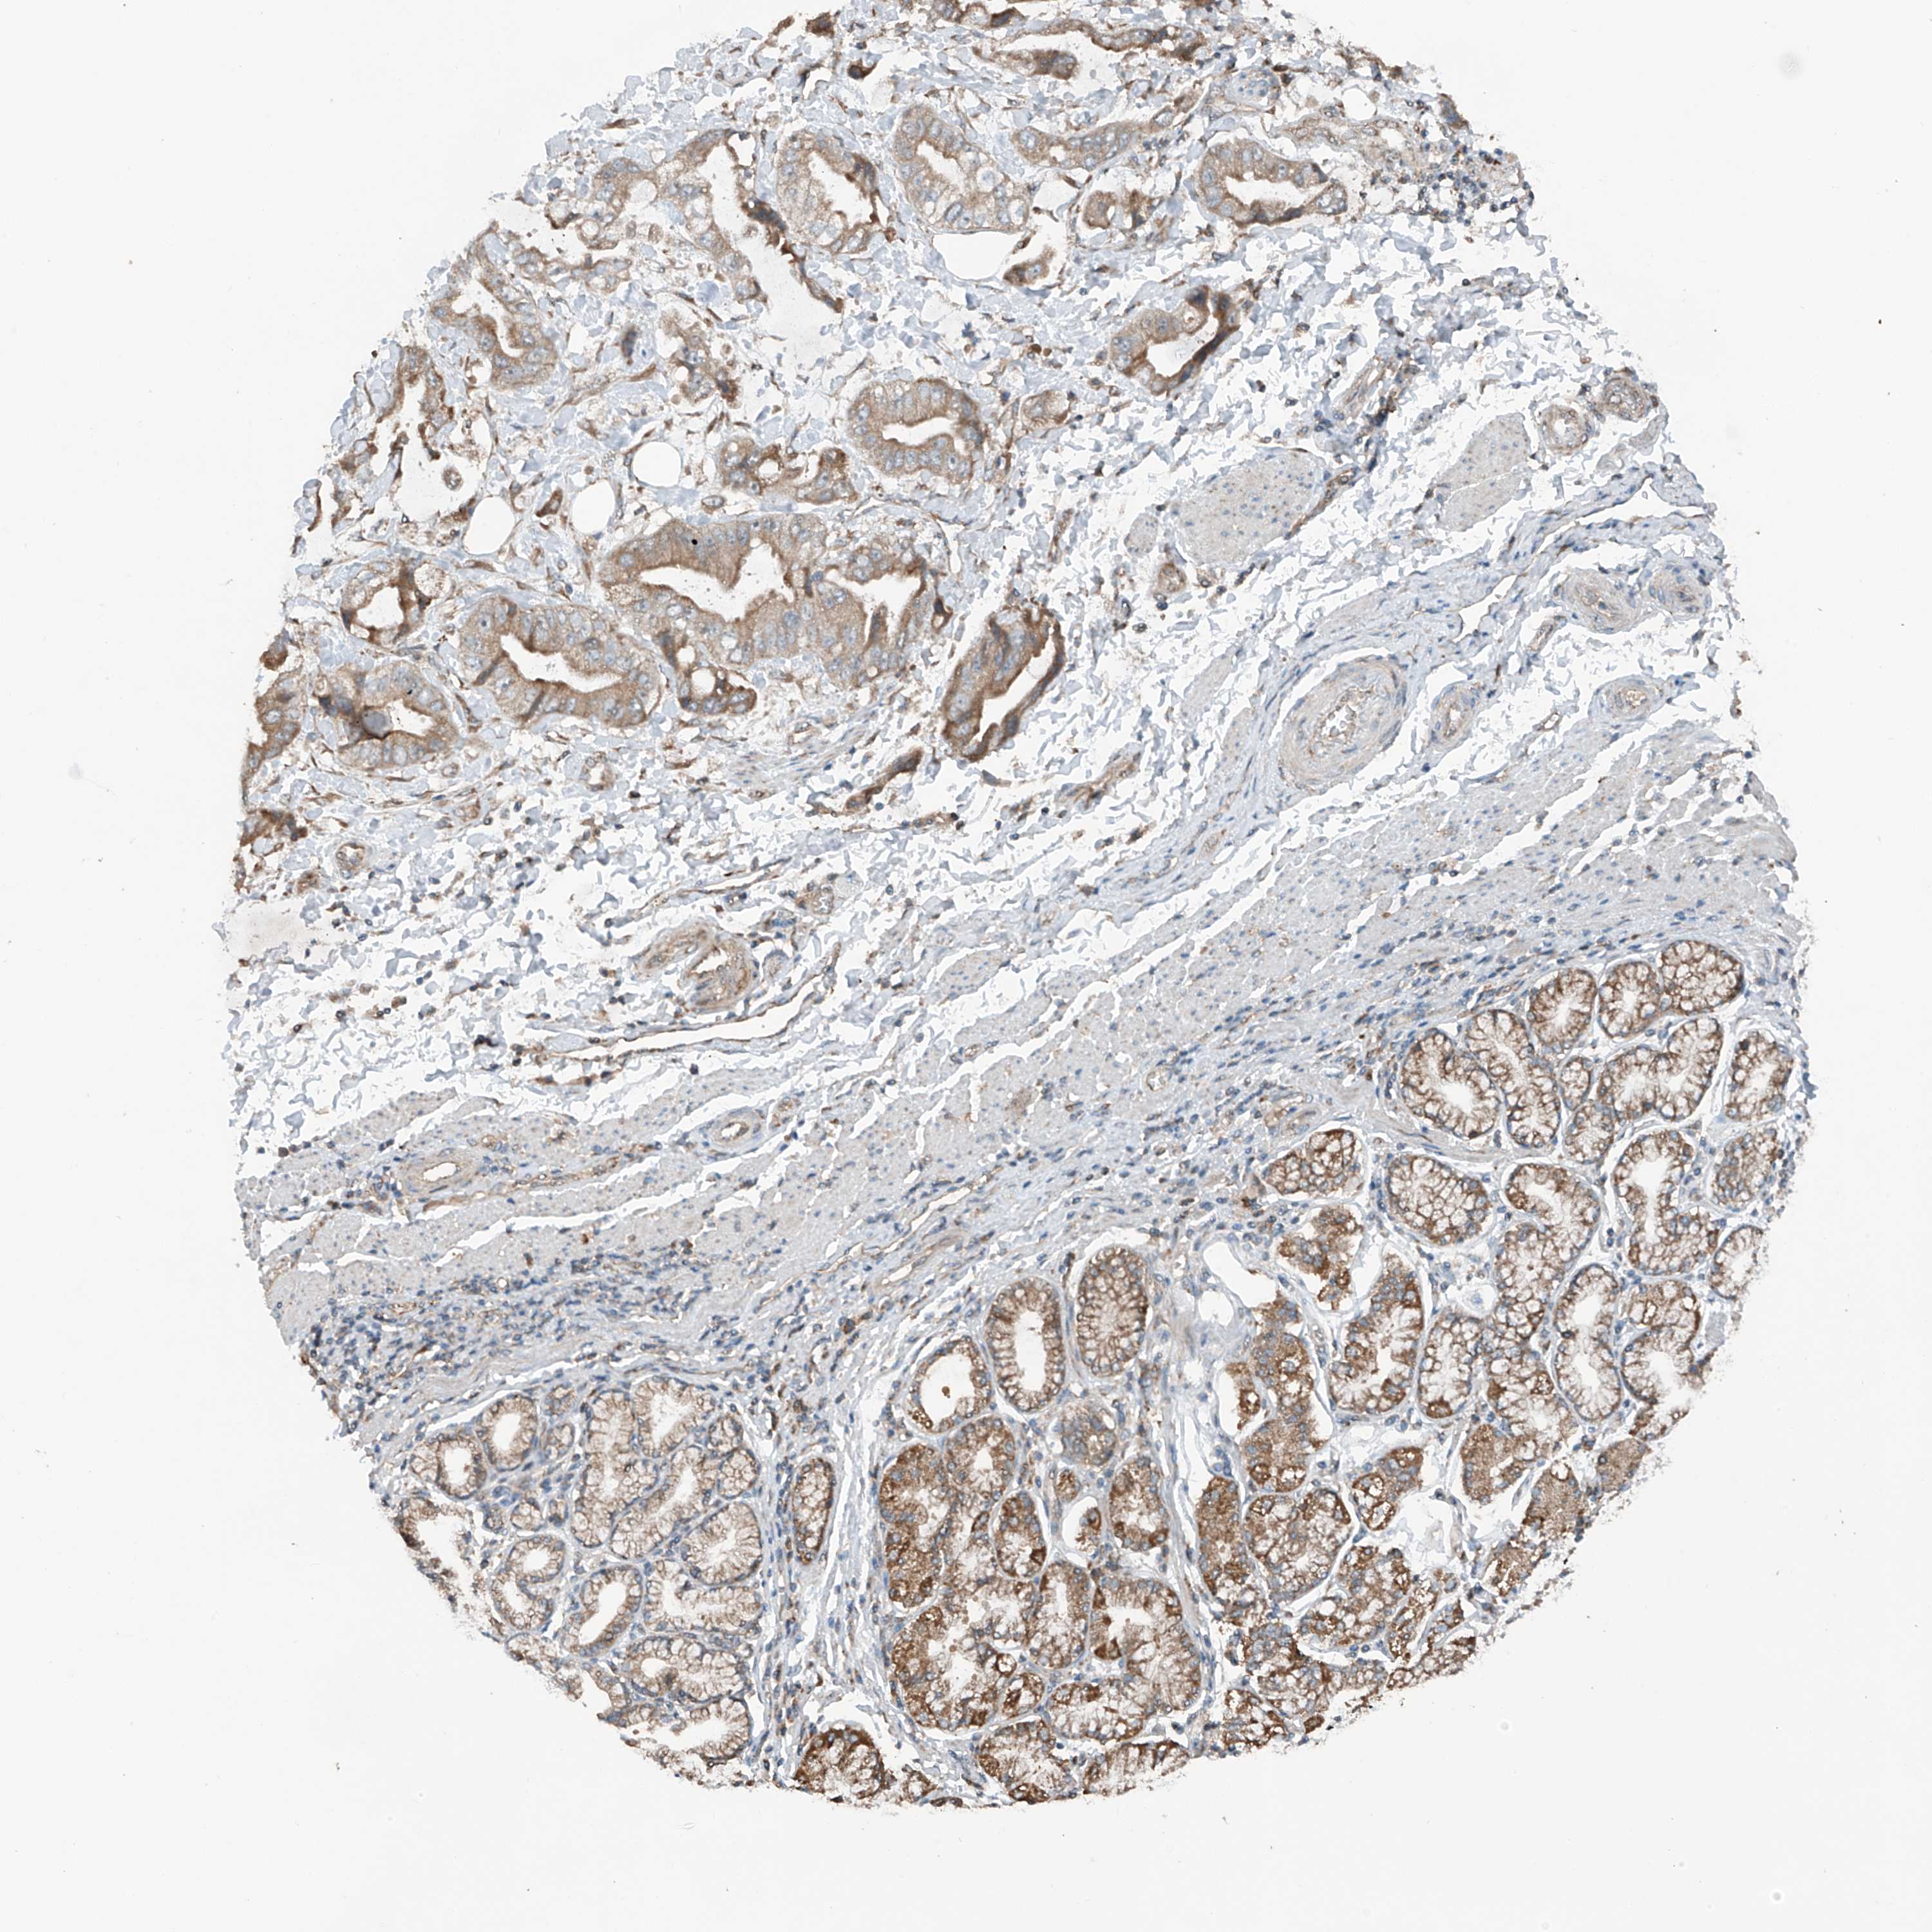

STOMACH CANCER - Protein expressioni

A mouse-over function shows sample information and annotation data. Click on an image to view it in a full screen mode. Samples can be filtered based on level of antibody staining by selecting one or several of the following categories: high, medium, low and not detected. The assay and annotation is described here.

Note that samples used for immunohistochemistry by the Human Protein Atlas do not correspond to samples in the TCGA dataset.

Antibody stainingi

Antibody staining in the annotated cell types in the current human tissue is reported as not detected, low, medium, or high, based on conventional immunohistochemistry profiling in selected tissues. This score is based on the combination of the staining intensity and fraction of stained cells.

Each image is clickable and will lead to virtual microscopy that enables deeper exploration of all samples and also displays staining intensity scores, fraction scores and subcellular localization as well as patient and tissue information for each sample.

Antibody HPA028992

Antibody HPA028993

Staining

High

Medium

Low

Not detected

Intensity

Strong

Moderate

Weak

Negative

Quantity

>75%

75%-25%

<25%

None

Location

Nuclear

Cytoplasmic/membranous

Cytoplasmic/membranous,nuclear

Adenocarcinoma, NOS